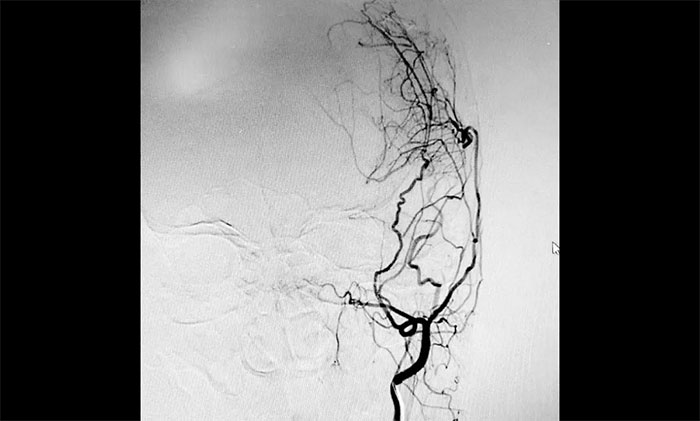

▲ DSA显示左侧脑供血侧支循环已逐步建立

7月中旬,范先生遵照医嘱来医院复查,不仅体重回到了脑出血前的水平,精神状态也明显好转。再次行DSA检查显示,左侧大脑中动脉远端血管丰富,表明该侧脑供血侧支循环已逐步建立,缺血脑组织得到了及时挽救,符合手术预期。